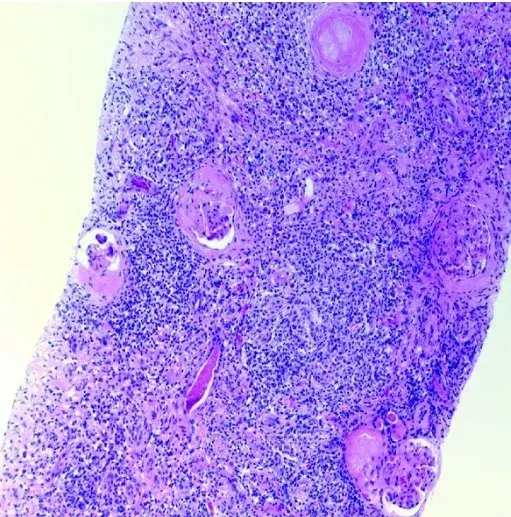

Conforme evolução da doença a paciente apresentou um novo _flare_ renal com proteinúria de 6 g/g. Foi submetida a biópsia renal, que identificou lesões ativas e crônicas, como proliferação mesangial, lesões wire-loop e depósitos subendoteliais, intramembranosos, subepiteliais e mesangiais na microscopia eletrônica. Sendo tratada com novo pulso de metilprednisona, micofenolato de mofetila 1000 mg/dia e prednisona 10-15mg/dia. Foi feita uma tentativa de associação de tacrolimo ao esquema, mas foi descontinuado devido ao descontrole da glicemia. Neste momento a paciente também tinha o diagnóstico de **diabetes induzido pelo excesso de corticoides** e estava em uso de insulina há 7 anos, com uma hemoglobina glicada de 8,5%.

A microscopia de luz revelou glomérulos com lesões insudativas, hialinização arteriolar e proliferação mesangial (Figura 1A), mas **nenhuma** lesão ativa da nefrite lúpica foi identificada. A imunofluorescência mostrou **apenas** deposição linear de IgG ao longo da membrana basal glomerular com escassa deposição granular (Figura 1B). A microscopia eletrônica demonstrou apagamento do processo podocitário e espessamento da membrana basal.

Esses achados foram diagnósticos de **nefropatia diabética sobreposta a lesões crônicas de nefrite lúpica**.